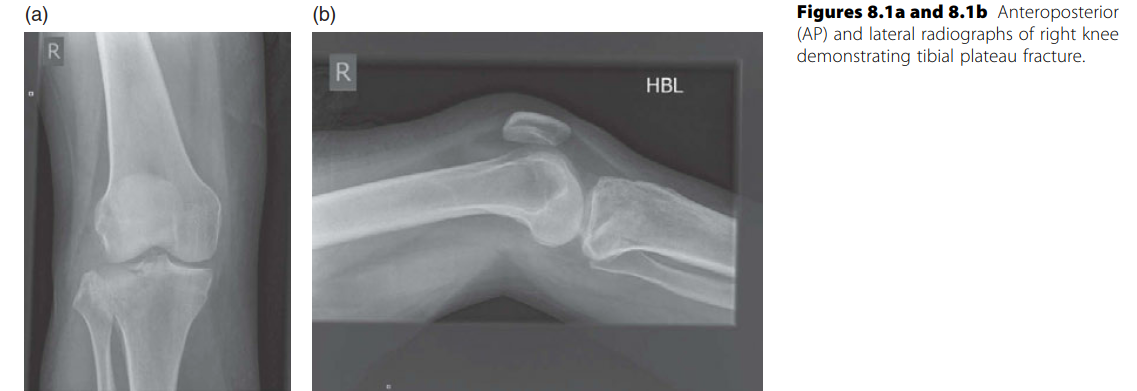

Lower limb Trauma Structured oral examination question 3 Minutes 1 and 2 EXAMINER : A 49-year-old lady fell o…